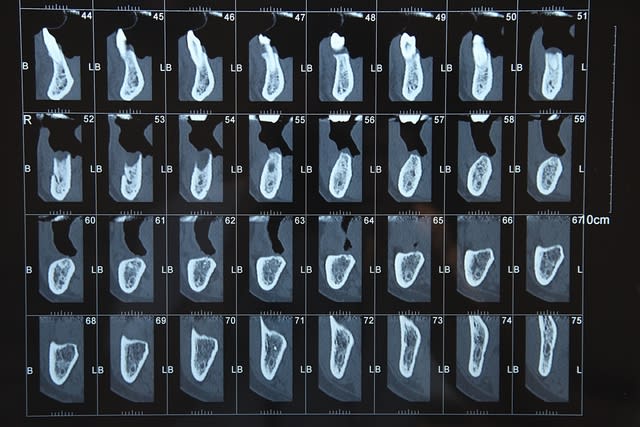

Voici le scan:

Feyimg 8735 c2cykn - Eugenol

Feyimg 8733 kvghzr - Eugenol

Feyimg 8734 fc50c4 - Eugenol

dommage qu'on voit pas ce qu'il y a dans les coupes 50/60...

sinon, c'est une autoroute....là un "all on" 5 ou 6 implants...çà le ferait bien...;-))

Voilà voilà

Feyimg 8742 sgd7sv - Eugenol

je confirme...autoroute...

j'aimerais bien en avoir des comme çà tous les jours à mon cab...;-))

heu...j'ai peut être pas très bien chaussé mes lunettes pxav...mais les repères sous les coupes...si on s'en réfère à la mesure de référence donnée tout à droite de la dernière planche de scan( "règle" de 10cm)...semblent être des repères de plan de coupe de 2mm...

mis à part dans la zone des incisives où là c'est plus étroit (normal)...à partir des canines, on a des crêtes d'au moins 6/8 mm minimun....

peut être que gribouille pourrait confirmer...mais si c'est le cas...je sais pas ce qu'il te faut pour planter....

par contre, d'accord avec toi pour la qualité, ou santé osseuse...il faut peut-être être assez prudent sur ce cas